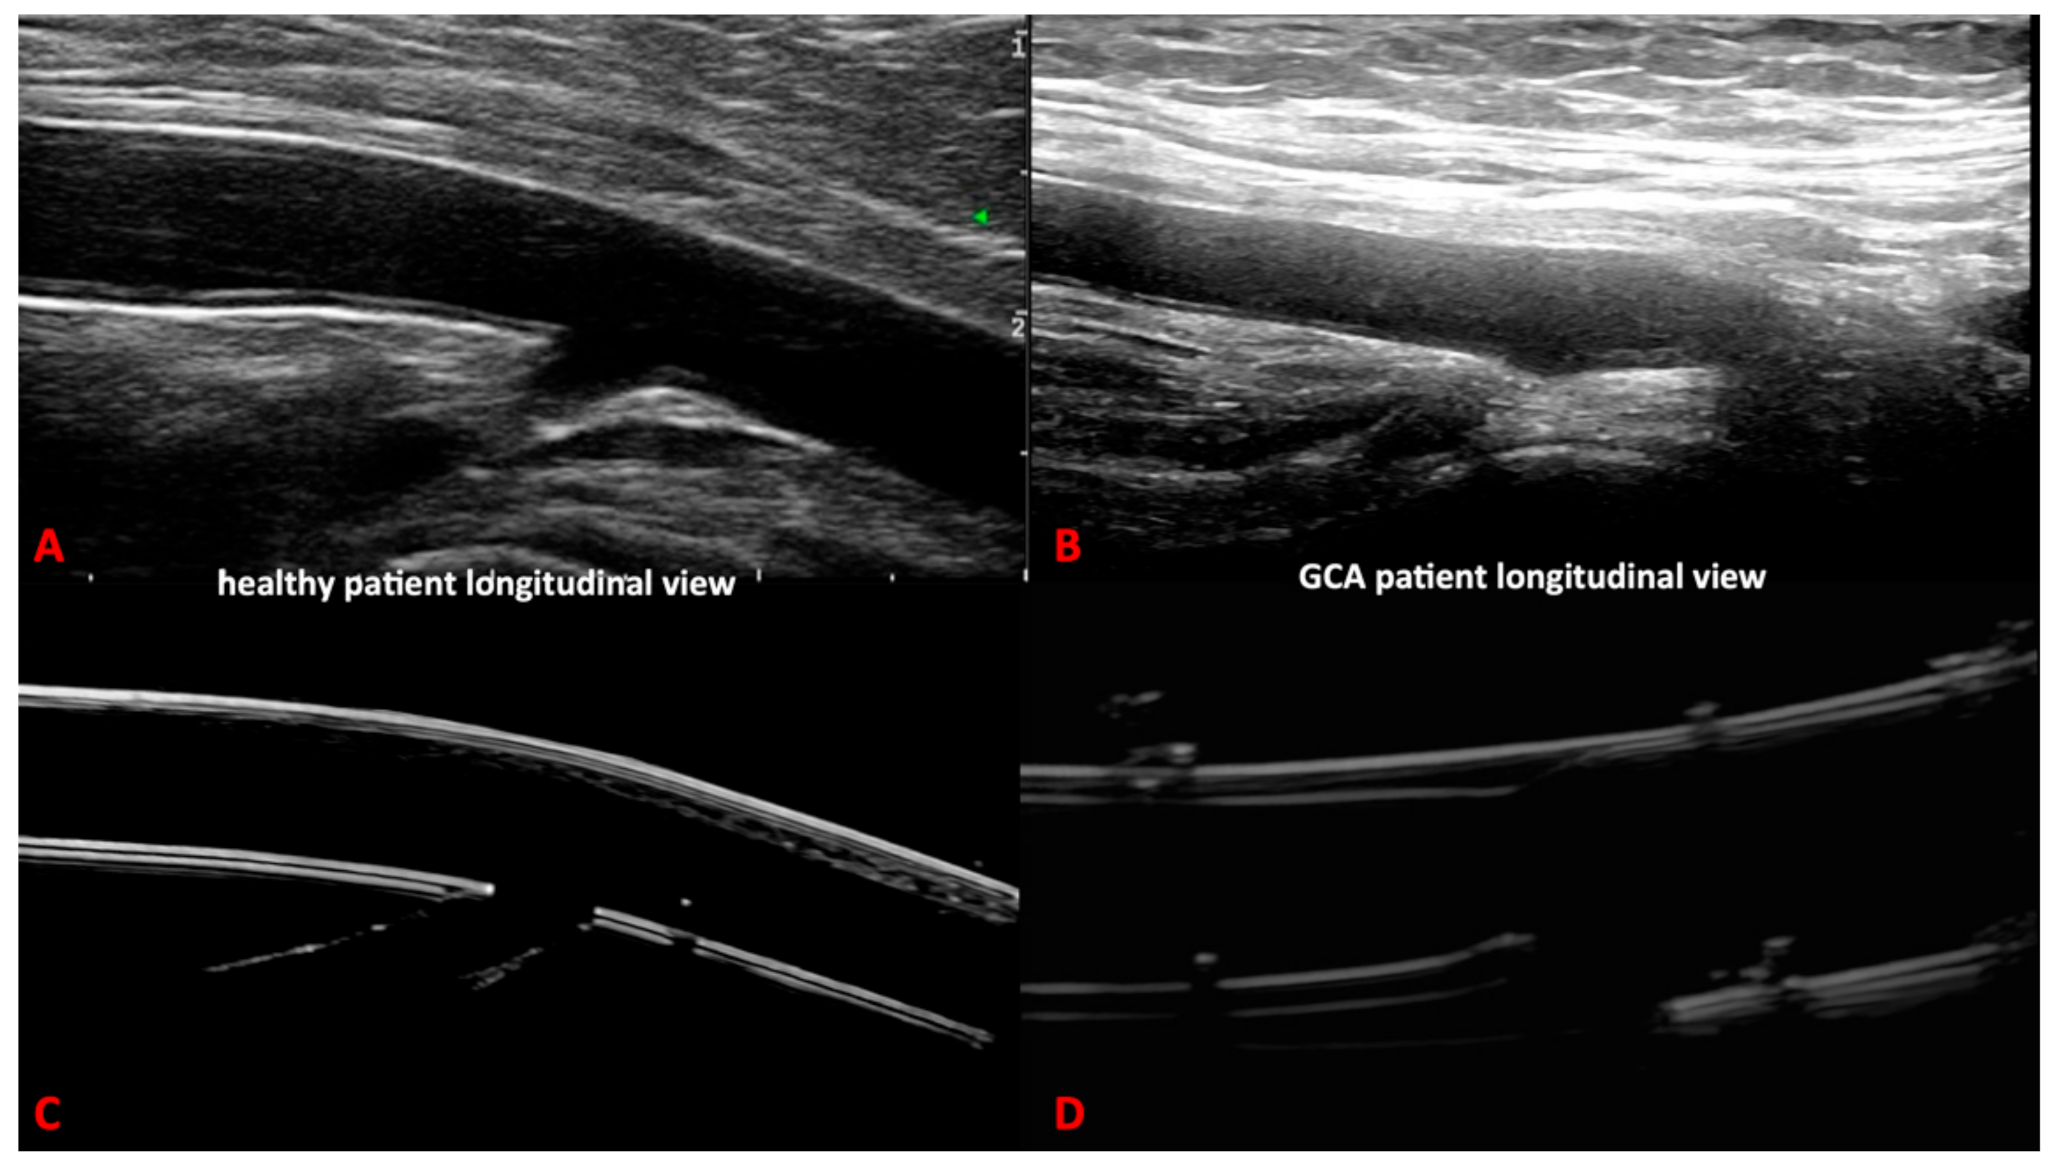

Our 3D printed artery models fulfilled the OMERACT definitions of normal and pathological temporal and axillary arteries in GCA [5] (Figure 4 and Figure 5). In addition, we were able to replicate the IMT of the corresponding arteries, allowing the measurement of the IMT values of the normal and pathological arteries. These values corresponded to the published cut-off values [20,21,22] for ultrasound diagnosis in GCA of the temporal or axillary arteries.

Figure 5. Comparison between ultrasound images of the temporal artery of the 3D printed models of healthy (D,E) and pathological setting (F) and real ultrasound images in healthy (A,B) and giant cell arteritis patients (C).